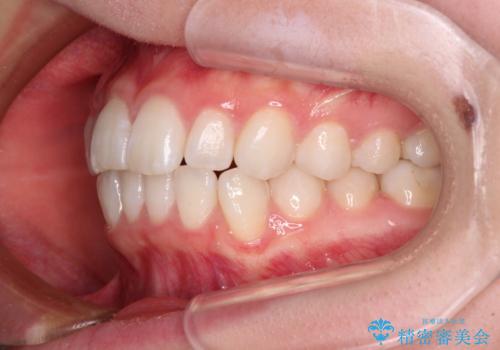

- 前歯の出っ歯と口元の閉じにくさを気にして来院された患者様です。

口元を積極的に引っ込めるために、上下左右の小臼歯4本を抜歯することとしました。

4本の歯を抜歯したことで、飛び出していた口元が引っ込み、横顔が大きく改善されました。